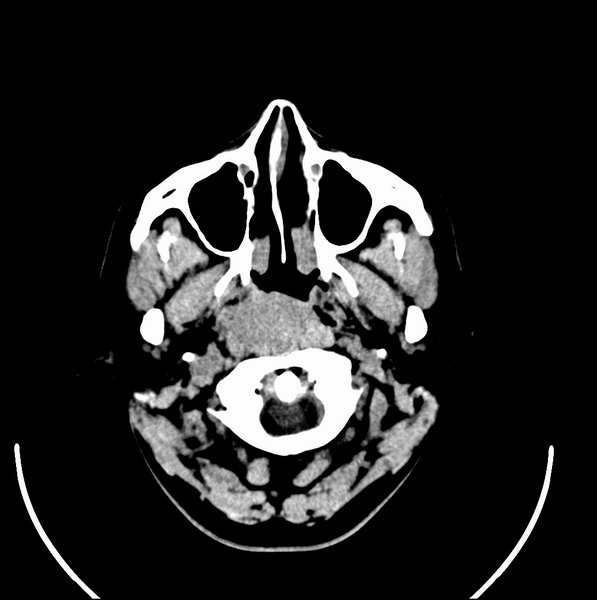

扫描示鼻咽腔不对称,中度狭窄,右侧咽隐窝消失,局部软组织肿块,鼻咽右侧壁增厚形成肿块,突入鼻咽腔,肿块平扫呈等密度,肿块向深部侵润,右侧翼内外肌受侵,右侧咽旁间隙变窄;向后生长,头长肌界线欠清,向后上生长侵犯同侧颈动脉鞘区。双侧海绵窦增宽,内见软组织影与鼻咽部肿块相连。考虑鼻咽癌。鼻咽癌主要是放射治疗,且效果较好;到当地有治疗设备较大医院治疗即可。

典型鼻咽癌侵犯右侧海绵窦(对放疗敏感)

还是先确诊,如果是鼻咽癌,一般行放射治疗;这例患者我首先考虑鼻咽癌